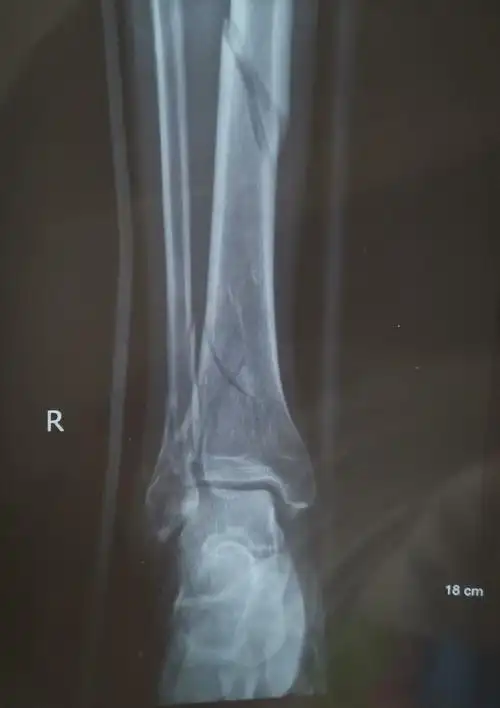

胫骨骨折伴踝关节骨折手术分享